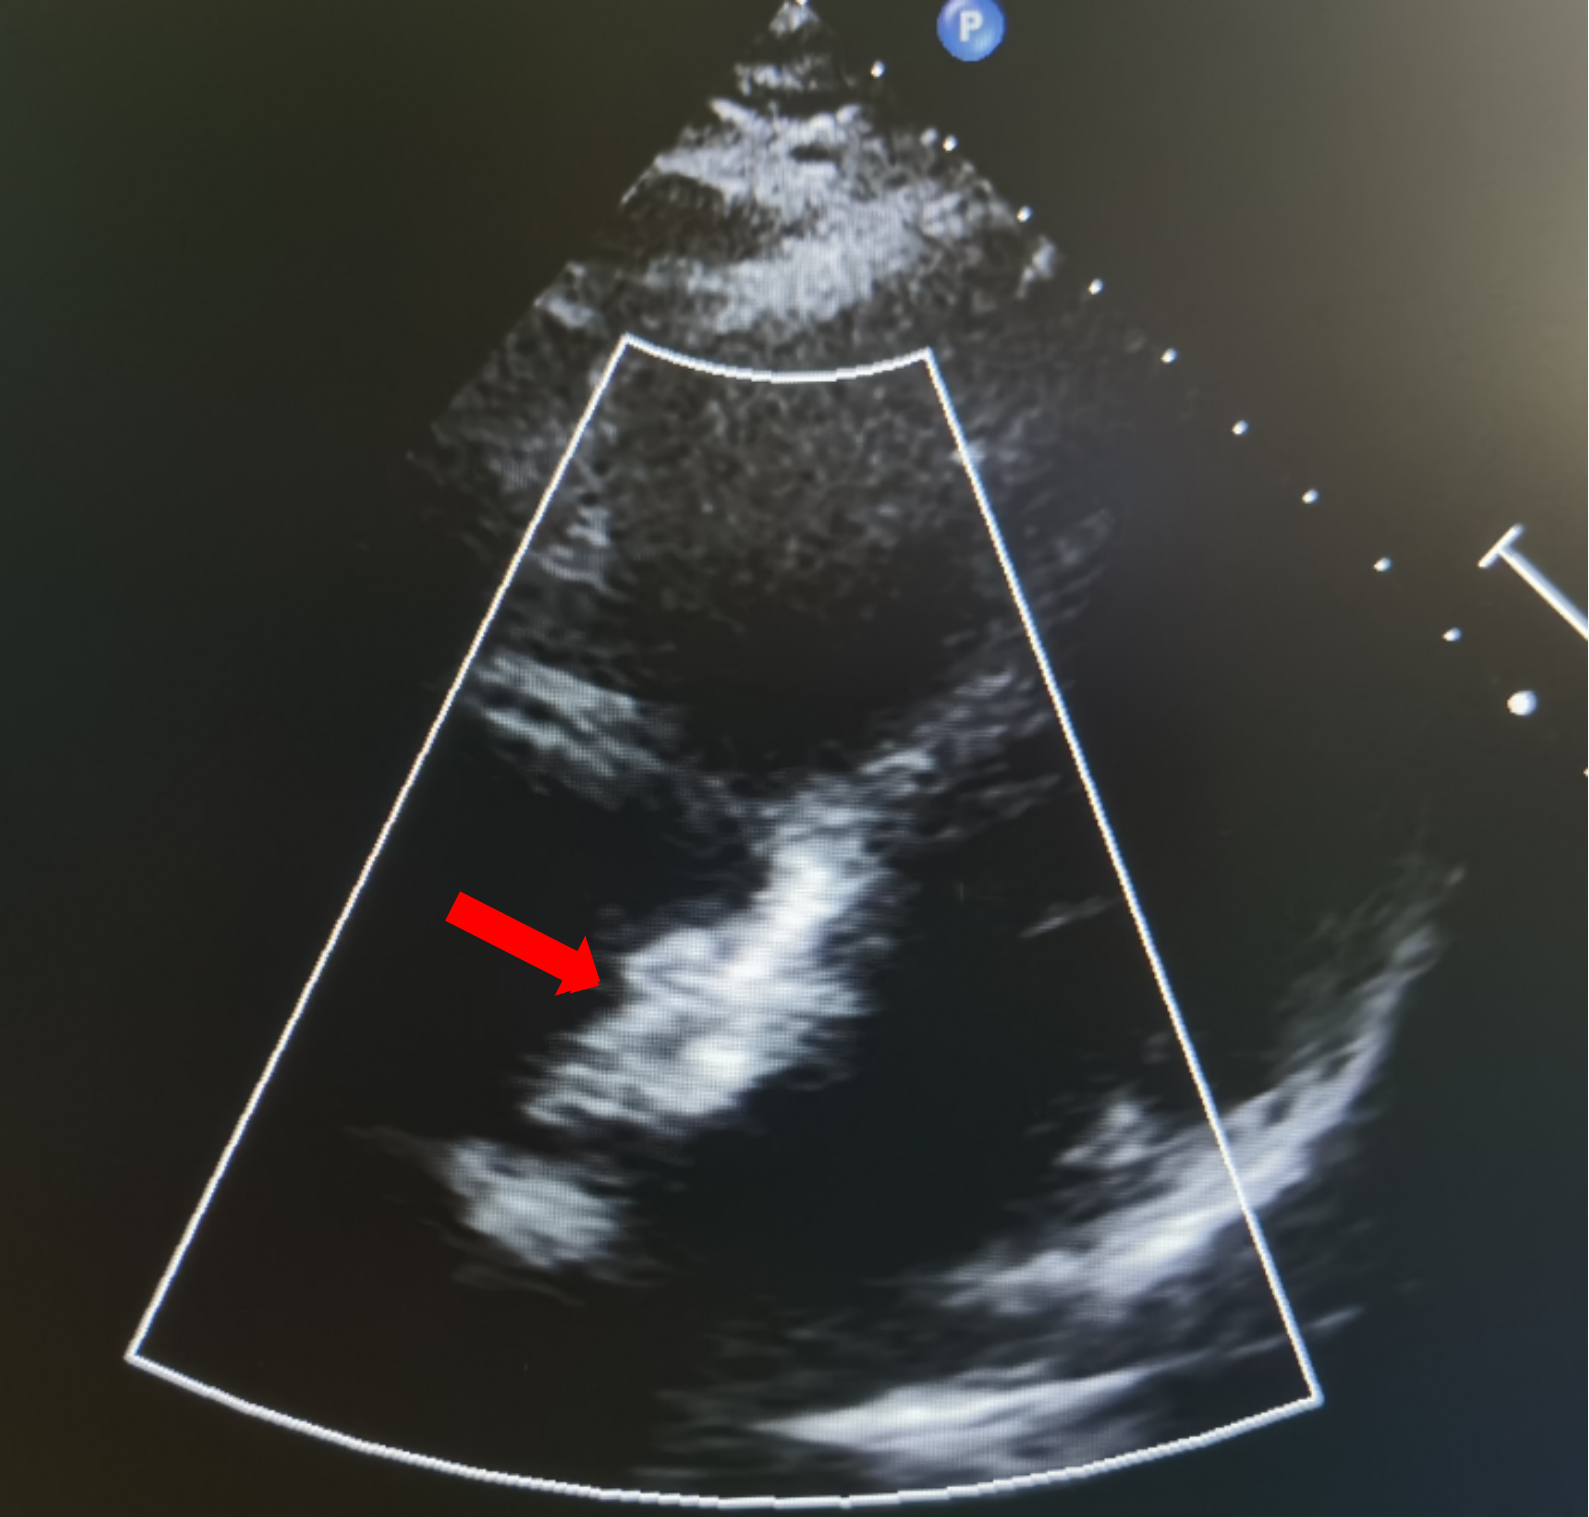

二维超声心动图:患儿年长,体脂厚,切面探查显示不清。心脏位置及连接正常。右房右室增大、主动脉无增宽,肺动脉增宽。房缺缺损约17.7mm(继发孔型),二维显示房间隔缺损约15.9mm,彩色束宽约17.3mm(软边约10.8mm,非飘软)。胸骨旁四腔:距二尖瓣缘26.0mm,距房顶缘约7.2mm;剑下两房心:房隔总长约45.6mm,距上腔缘约14.6mm,下腔缘约19.9mm。室间隔完整,房室瓣开放活动正常,左位主动脉弓。左冠状动脉开口位置正常,右冠状动脉开口显示不清。

超声提示:房间隔缺损

术中复测及封堵策略:术中超声复测缺损大小约19.1×17.9mm,经综合评估后,决定经股路径介入,选择BDASD-I 28可降解封堵器、16F可降解封堵器介入输送系统进行封堵,手术全程通过超声+DSA引导进行。

超声下确定封堵器左右两盘骑跨在房间隔两侧

沿房间隔可见封堵装置,沿其周围未测及残余分流。

超声提示:ASD封堵术后,无残余分流。

房间隔可见封堵器回声,位置固定,形态良好。房水平未见残余分流信号。

术后即刻超声检查显示封堵器位置正确、形态良好、夹持稳定,无残余分流。术后第1天和第2天的随访超声进一步显示房间隔可见封堵器回声,位置固定,形态良好,且房水平未见残余分流信号。